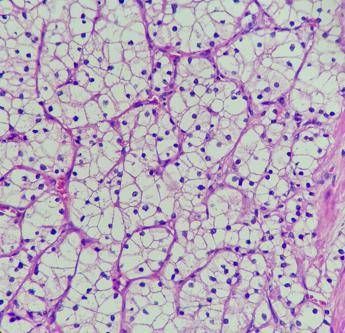

Studio, Tki e immunoterapia più efficace di sunitinib in carcinoma a cellule renali